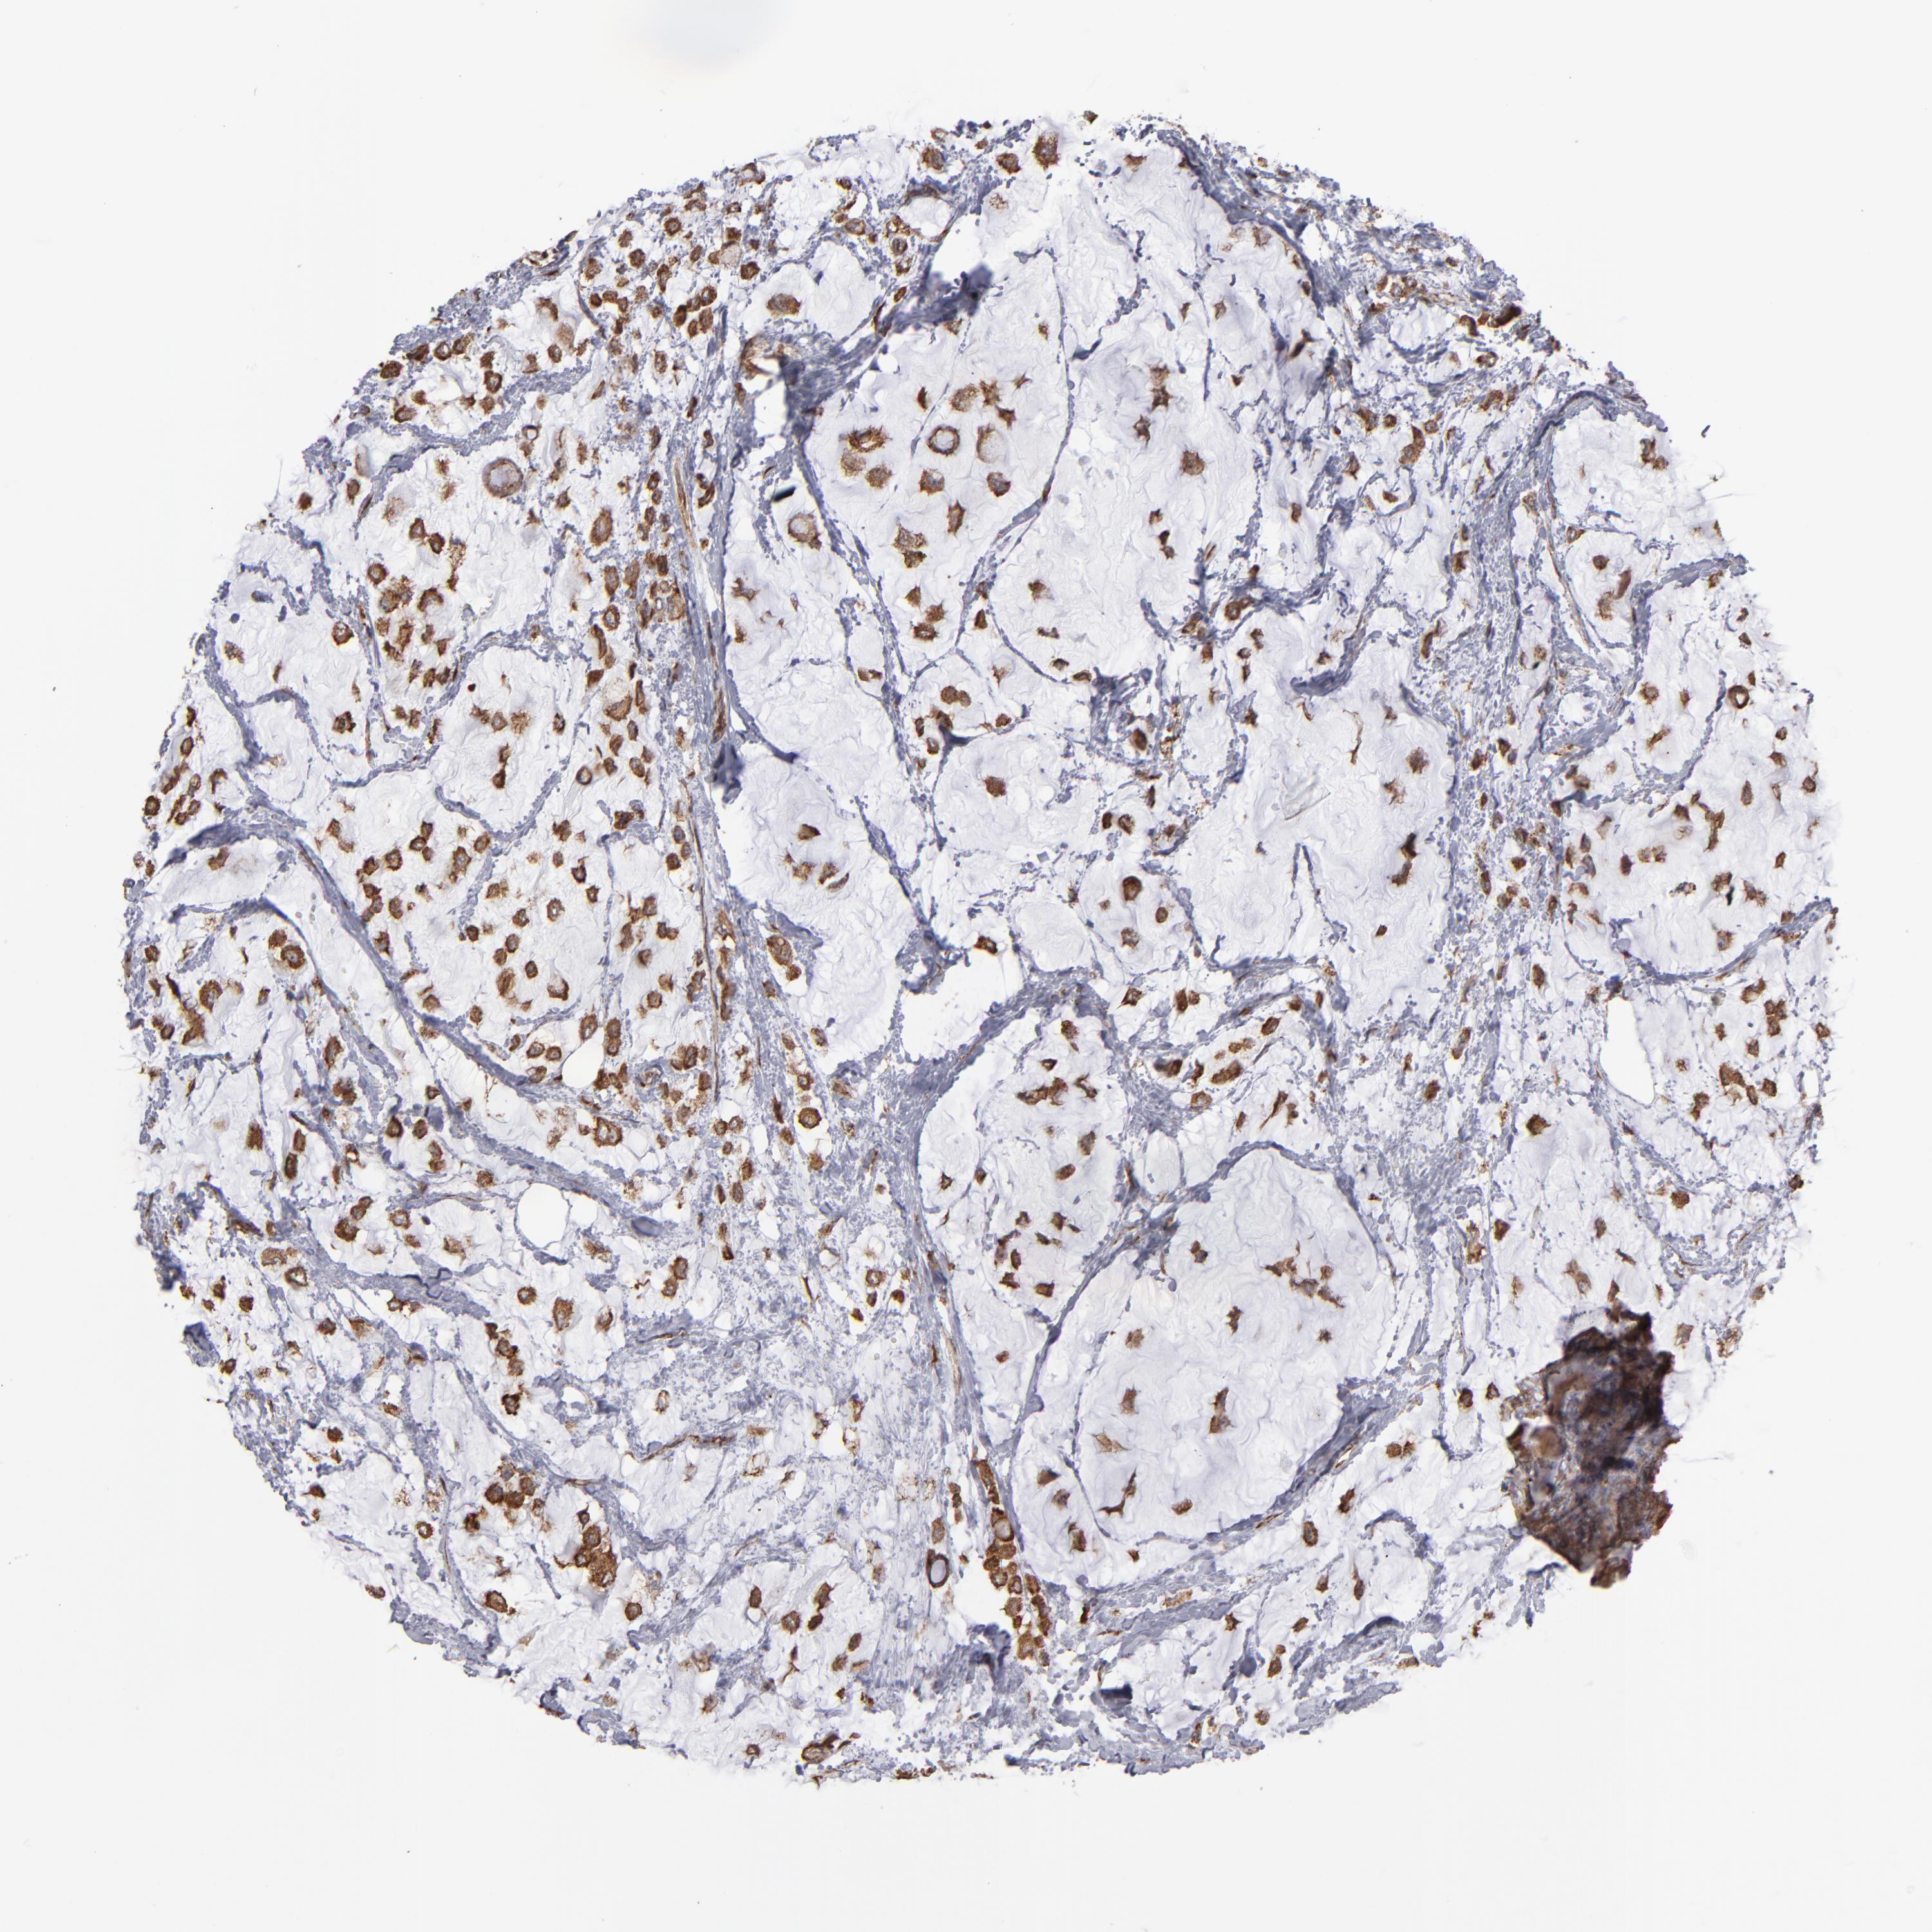

CANCER BREAST CANCER Show tissue menu

BRCA TCGA BRCA VALIDATION PROTEIN EXPRESSION